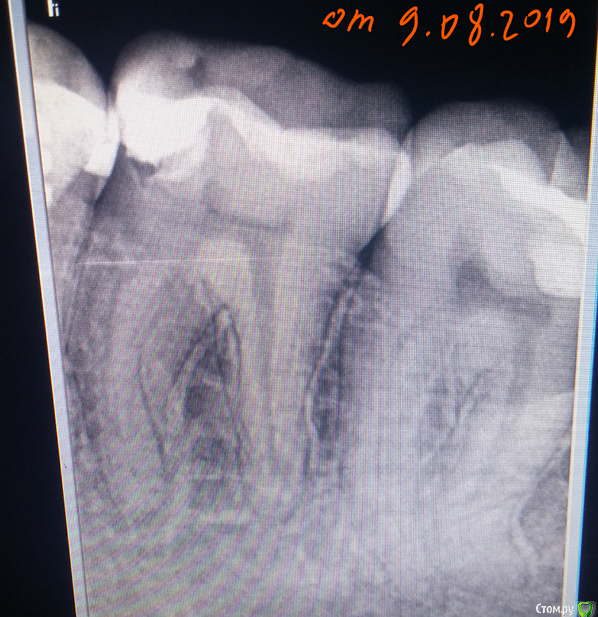

dentifree Опубликовано 19 августа, 2019 Поделиться Опубликовано 19 августа, 2019 Здравствуйте. !9.08.2019 заломило нижную челюсть в районе 6-го зуба.(слева). тупая непрерывная боль на весь день.В этот же день лечить не получилось. но удалось сделать прицельный снимок 6-ки.на второй день прошло.на третий день 11.08 опять заломило, + добавилась весьма сильная боль при накусывании на 6, и 7 зубы. на холод реакции не было., или была очень слабая.12.08. доктор поставил диагноз пульпит 6-го зуба, почищены каналы, после контрольного снимка, диагноз изменил на периодонтит. в этот же день поднялась температура до 38, на след.день спала.назначены антибиоткики,. сначала было улучшение. 6-ка и 7-ка перестали реагировать на накусывание.потом откатилось на ухудшение только 6-ки, но не на тот же уровень что до лечения.,появлялась температура в районе 37 -37,5после 5 дней, назначили еще один курс антибиотиков. на 19.08.2019 на накусывание по-лучше стало, но все-равно чувствительно, чуть ломит фоном в районе 6-ки, температура 37,5. Еще если двинуть челюсть влево->вбок, то ощущение будто что-то втыкается, боль от этого движения не сильная. верно ли диагноз поставлен ? и выбор лечения, ?его один раз вскрыли, запломбировали, и лечение только антибиотиками.Несколько лет назад, на другом зубе периодонтит, хотя бы 2 раза промывали каналы, и там все быстро прошло за 3-5 дней.в приложении снимки,1-й за неск. дней до обращения. (9.08.2019)2-й снимок 2 дня назад, снимок на другом аппарате.3-й (тот же второй) но с обозначенными местами которые смутили, стоит ли за них беспокоиться. ? На 3-м рисунке цифрами..Зеленая 1,2 — на какие-то зазоры похоже, протяженностью вдоль корня. Это норма ?Зеленая 3, в синем кружочке область, будто есть соединение с корнем 7-го зуба, могло ли в этой области как-то воспаление «перекинуться», что 7-ка на накусывание болел также сильно как и 6-й. ? Ссылка на комментарий

dentifree Опубликовано 19 августа, 2019 Автор Поделиться Опубликовано 19 августа, 2019 (изменено) 3-й снимок от 17.08.2019 Изменено 19 августа, 2019 пользователем dentifree Ссылка на комментарий